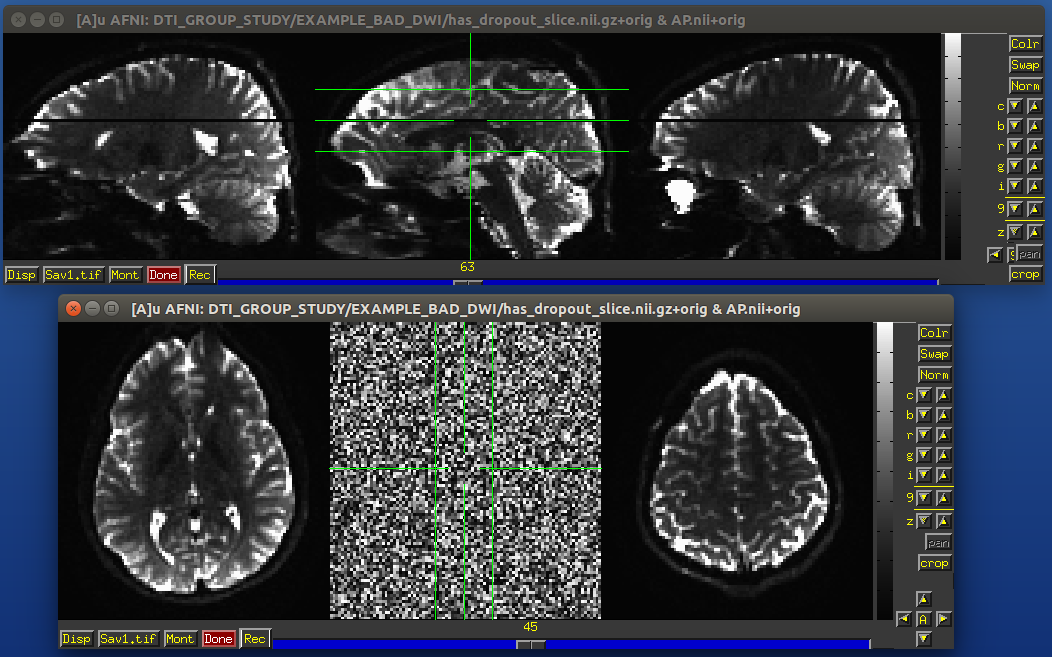

Example of subject motion artifact in a DWI volume that was acquired with an interleaved sequence (which is common).

Signal dropout

Signal dropout can occur due to susceptibility and excitation problems, sometimes limiting problems to just one slice. However, that slice is effectively useless, and one might consider filtering out this volume. (NB: in some cases, the volume could be left in if using an outlier rejection algorithm on a voxelwise basis for tensor fitting.)

Example of a dropout slice in a DWI volume.